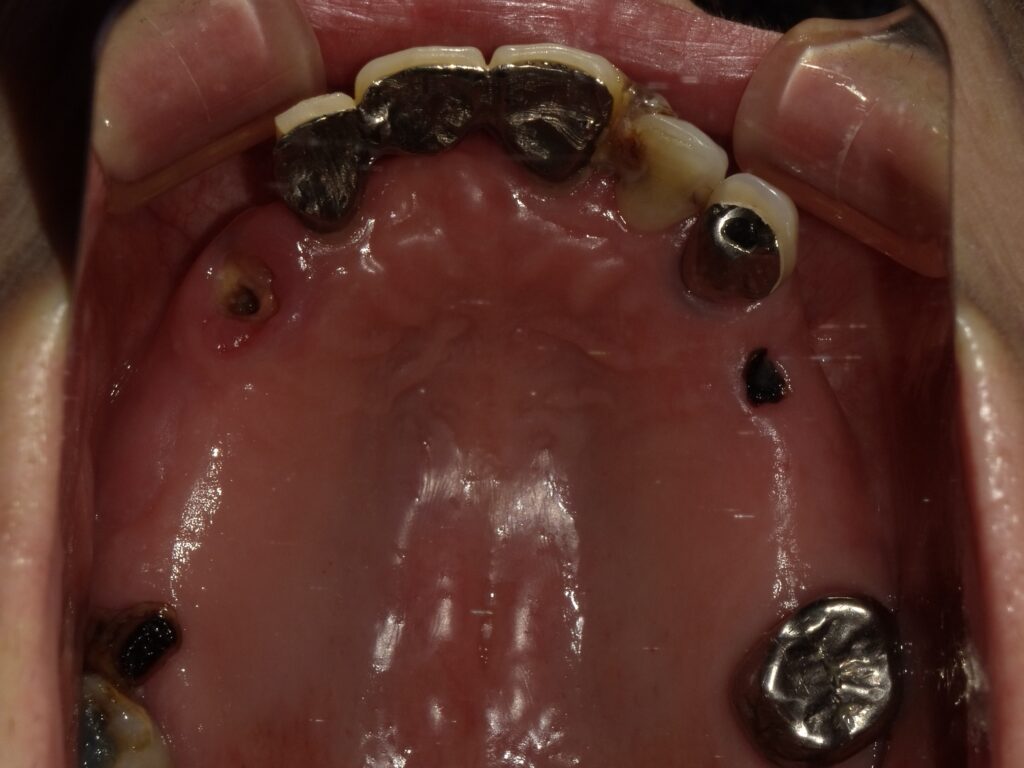

BEFORE

AFTER

主訴

全体的に見た目を綺麗にしたい。奥歯でしっかり噛みたい。

診断名・主な症状

臼歯部欠損

年齢

70歳

治療内容

インプラント埋入(右上4・6,左上4・6,右下6,左下6)

ジルコニアBr(右上3―左上3)

ジルコニア(右下5,左下5)

治療期間/

通院回数

インプラント 1年5ヶ月/13回

ジルコニアBr、ジルコニアクラウン 3ヶ月/10回

費用

インプラント: 2,552,000円

その他治療: 640,000円

合計 3,192,000円

*いずれも税込